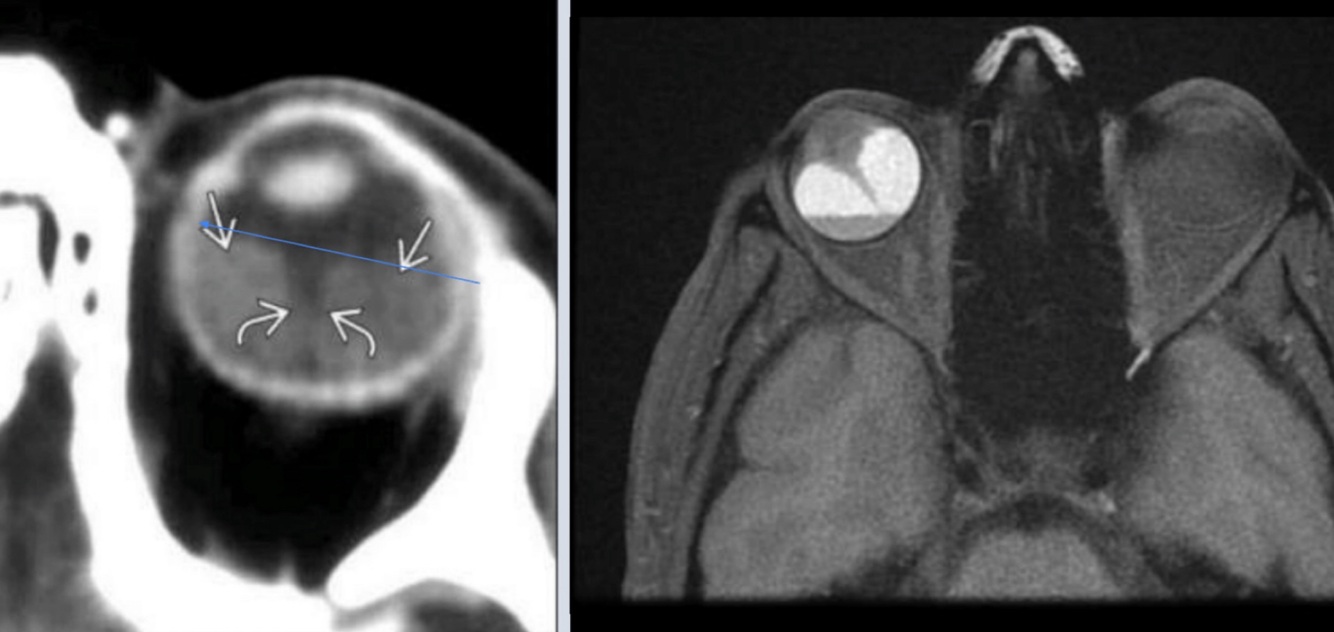

Hallazgo principal en orbitopatía tiroidea:

TC o MRI

A

Agrandamiento bilateral de músculos extraoculares

Hallazgos de la TC en orbitopatía tiroidea:

Relevancia de TC sobre MRI:

• Agrandamiento de músculos extraoxulares

• N. óptico estirado

• Exoftalmos

Enfermedad no complicada y plantear cirugía

Resonancia Magnética relevancia:

• Tratamiento

• Compromiso de N. óptico

Mejor estudio

T1